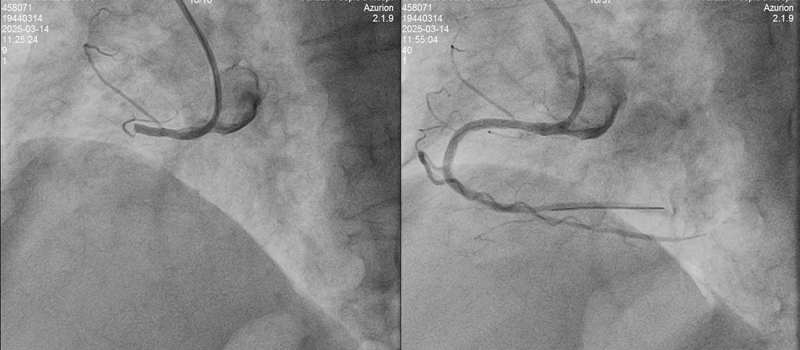

10:55,吴奶奶抵达玉环市人民医院,直接被送往DSA手术室。心脏造影显示三支血管严重病变:右冠近段急性完全闭塞,回旋支中段严重狭窄95%,前降支近段严重狭窄80%。

救心团队争分夺秒在吴奶奶梗塞的血管上抽出大量血栓,最终成功植入支架。入导管室至导丝通过26分钟,DtoW 32分钟。